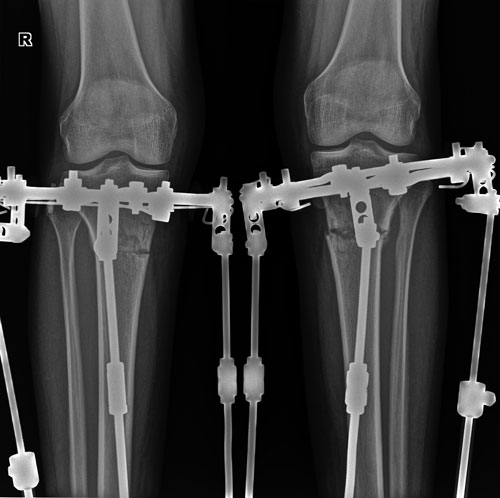

Дата операции 01.06.2018г.

Дата снятия аппаратов 29.08.2018г.

Срок сращения 88 дней.